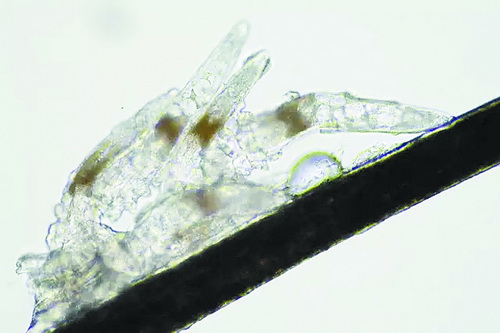

顯微鏡下長在睫毛中的螨蟲

冬天來了,氣溫降低,睫毛上的“隱形殺手”蠕形螨卻沒有要冬眠的意思。廈門大學(xué)附屬廈門眼科中心11月初開設(shè)蠕蟲性瞼緣炎門診以來,每天來查螨的市民都特別多,短短一個(gè)多月,已有近千人在顯微鏡下見到長期寄居在自己睫毛上,朝夕相處,卻素未謀面的蠕形螨。